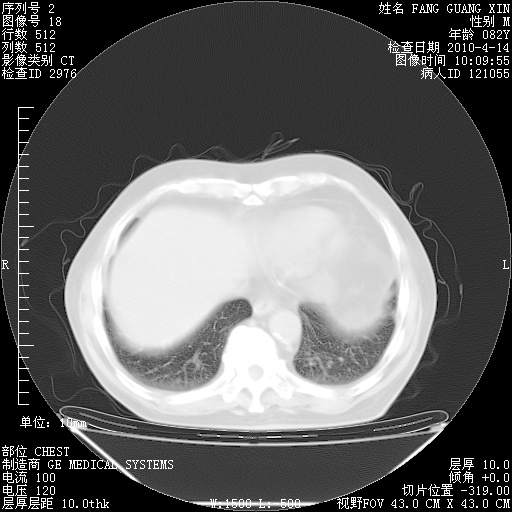

4月14日肺部CT

27.JPG

28.JPG

29.JPG

30.JPG

肺部CT平扫未见异常。